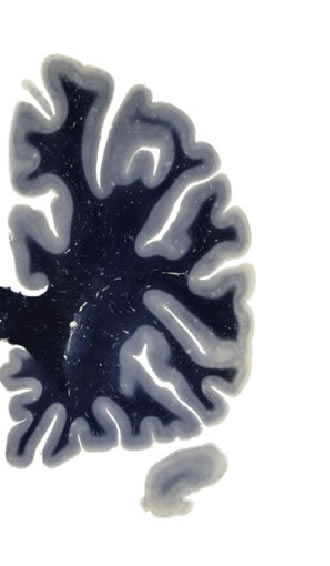

Hi-Resolution Sections · Cells (Nissl Staining) · Virtual Microscopy

Frontal sections (Nissl) from the Atlas Brain:

Slice ID:

r2-0770

Plate NR:

08-09

Position:

-24,1 mm